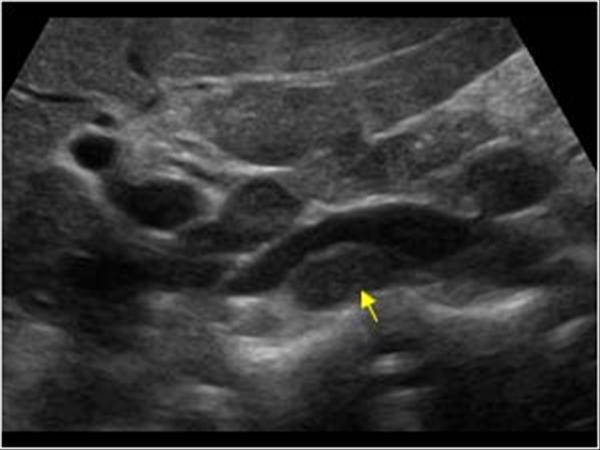

Mirizzi SYndrome

impacted stone in the cystic duct or GB neck

presence of two tubular structures representing the bile duct above the level of the cystic duct

Mirizzi SYndrome

impacted stone in the cystic duct or GB neck

presence of two tubular structures representing the bile duct above the level of the cystic duct